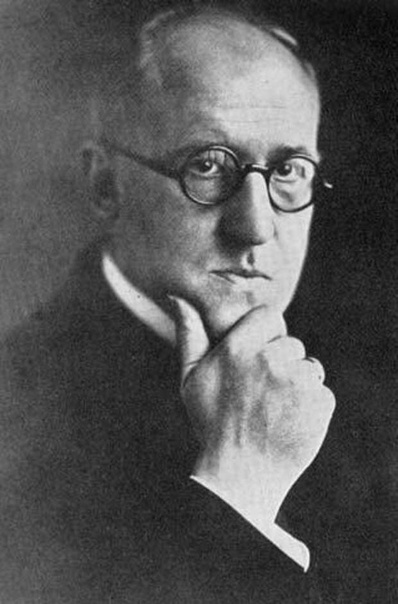

В начале 20-х годов ХХ века, когда во Франции шли исследования скрепи, немецкий врач Альфонс Мария Якоб описал пять случаев необычного заболевания человека, отличавшегося своеобразными клиническими симптомами и необычными изменениями в ЦНС у людей в возрасте от тридцати до пятидесяти лет. Обнаруживаемые у пациентов изменения были сходны только с изменениями, описанными ранее Гансом Герхардом Кройтцфельдтом, обнаруженными им при исследовании тела двадцатилетней девушки по имени Берта Е. Несчастная Берта при жизни страдала расстройствами зрения, навязчивыми мыслями об одержимости, нарушением координации движений и эпилептическими припадками. Учитывая эти обстоятельства, было принято решение назвать новое заболевание болезнью Кройтцфельдта-Якоба. Справедливости ради стоит сказать, что изменения, которые обнаружили Кройтцфельдт и Якоб, уже были известны учёным.

В начале марта 1957 года в изучение куру включился американский вирусолог словако-венгерского происхождения Карлтон Гайдушек. После этого началось интенсивное и плодотворное исследование неизвестной ранее болезни. Гайдушек был педиатром по образованию и вирусологом по призванию.